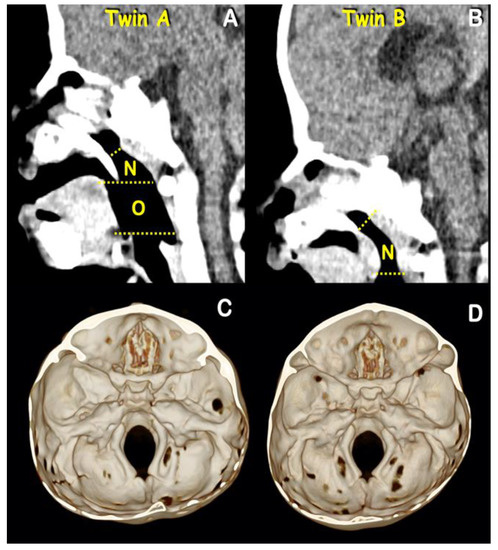

2. Patient Report

4.5. Increased Intracranial Pressure, Upper Airway Obstruction, and Sleep Apnea

4.6. Discordance in Monozygotic Twins